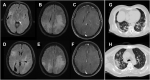

Brain MRI of the patient indicated diffuse confluent white matter hyperintensities.